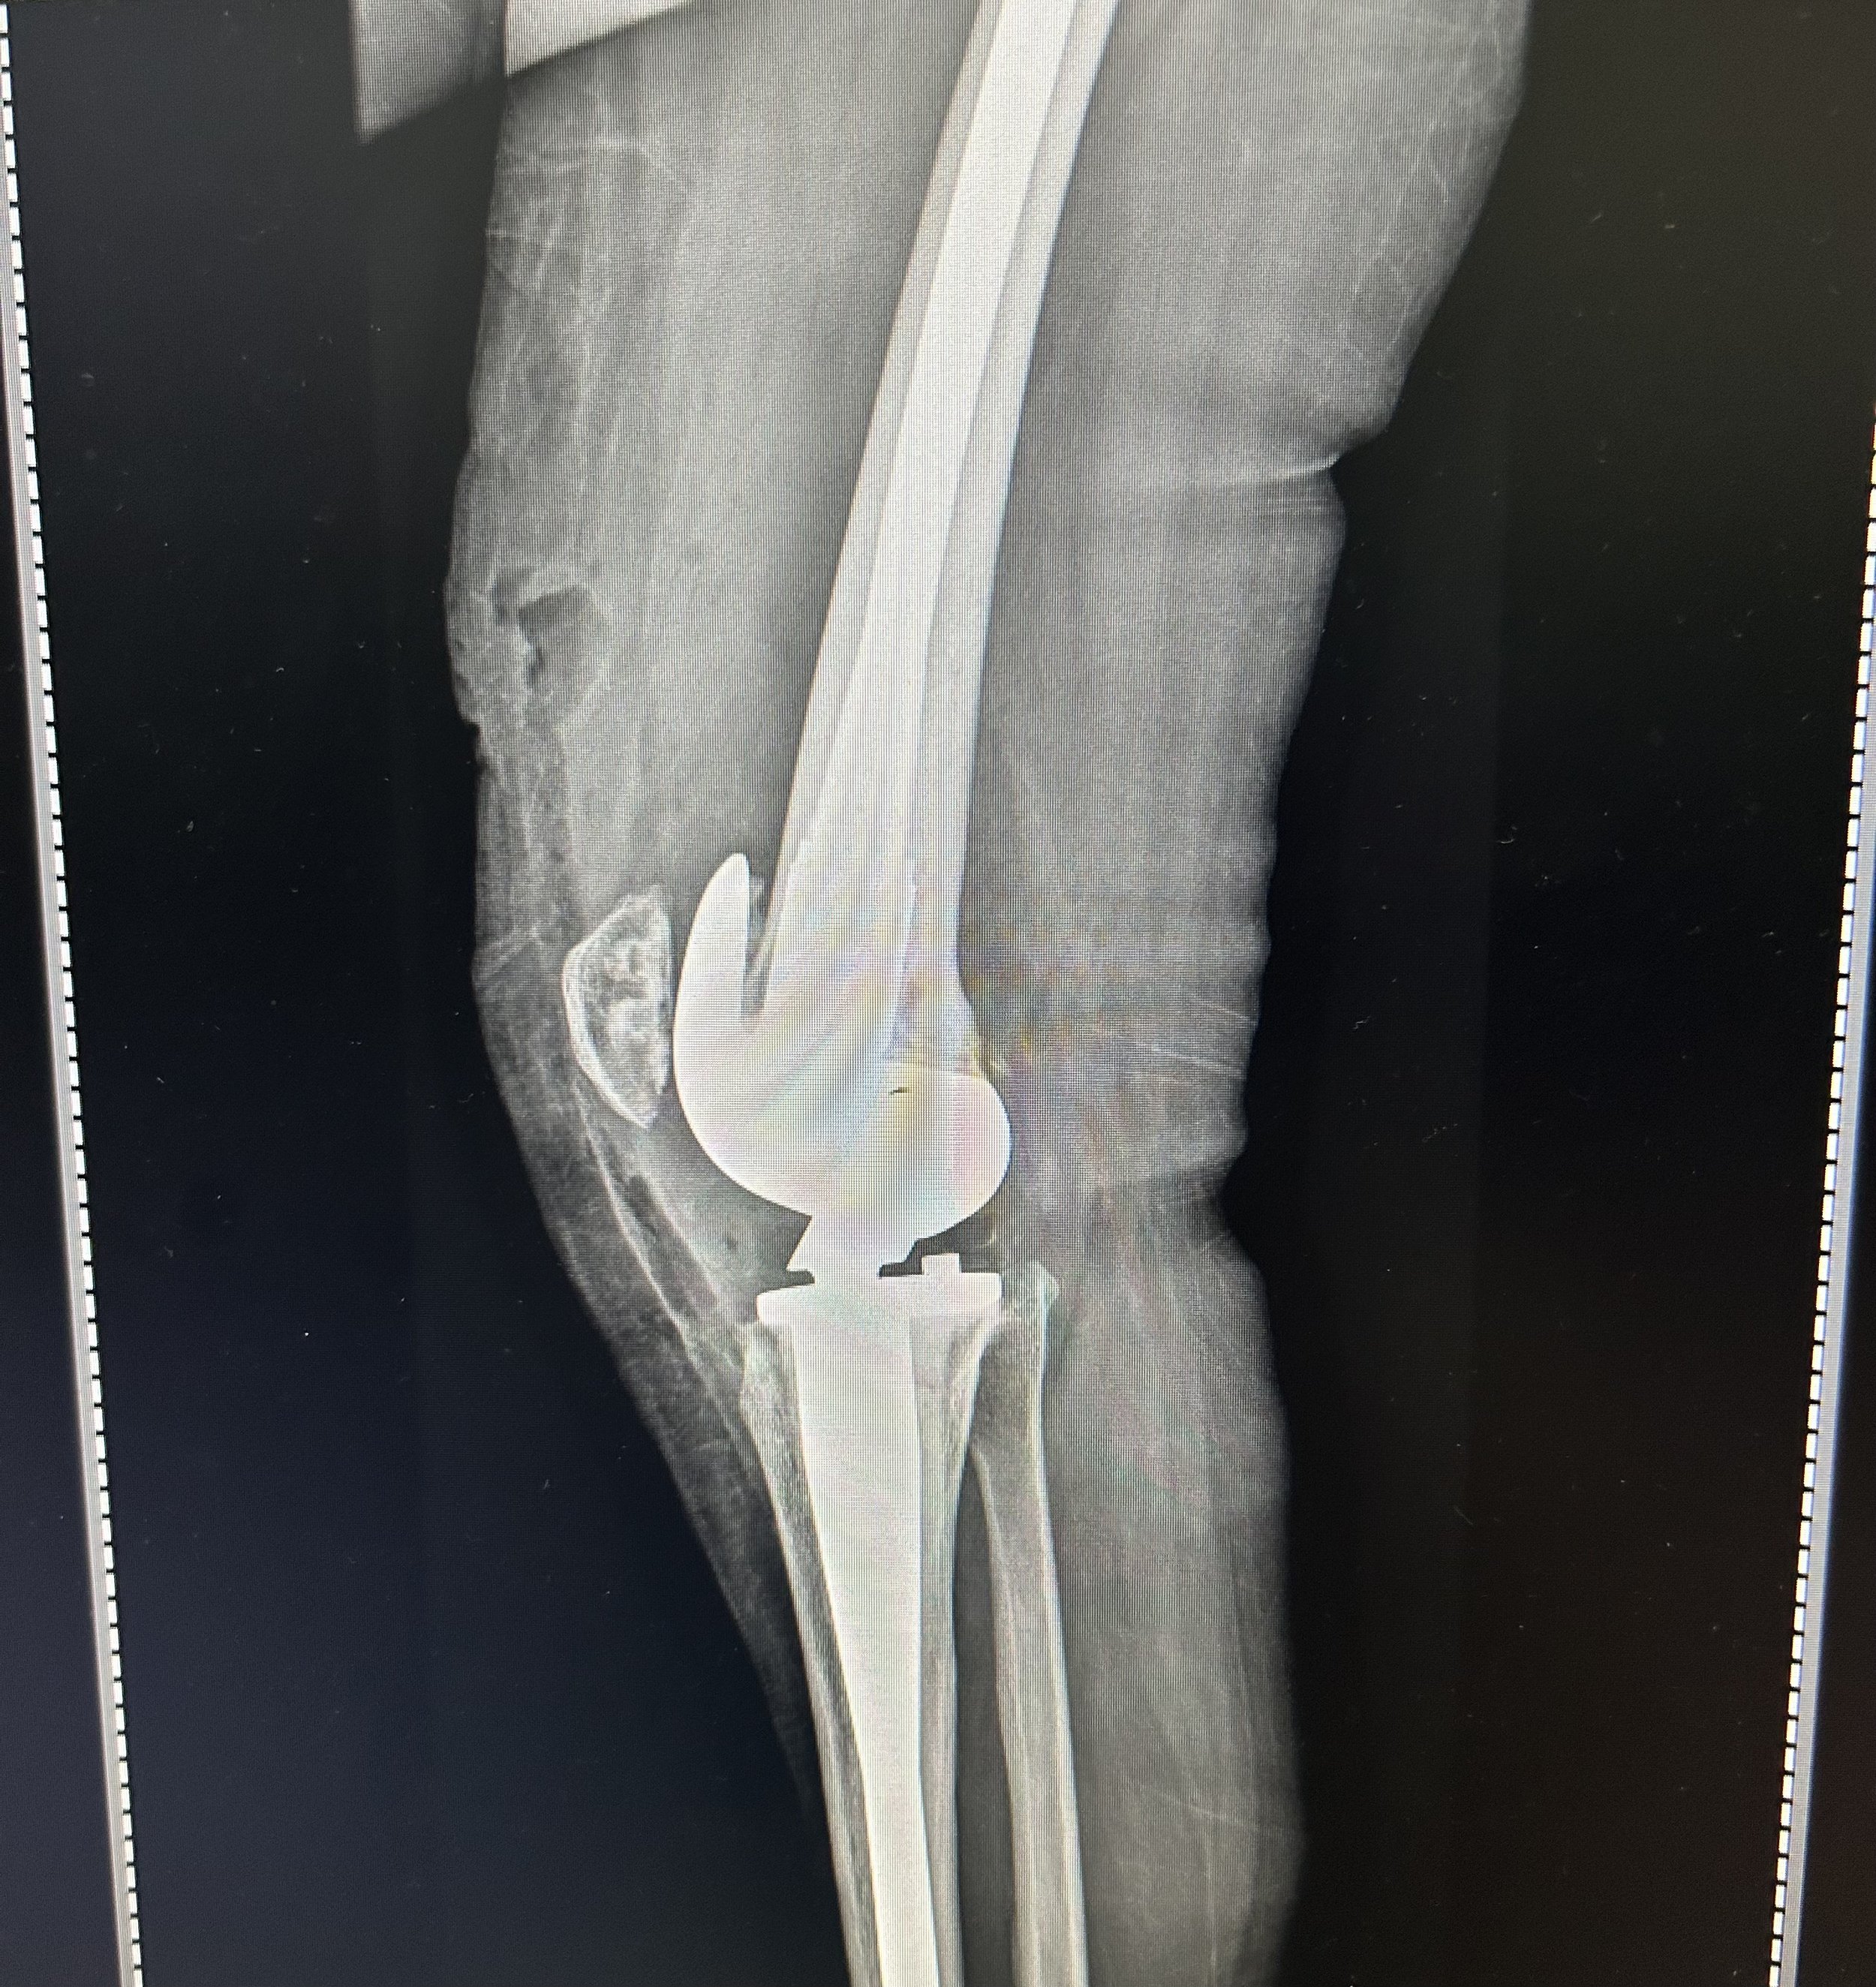

Sandra, a 29 y.o. The woman had been gathering firewood and reportedly fell 40 feet from a tree.  Because firewood is the primary source of energy for cooking in the rural areas of Guatemala, this practice often involves the women and children in the family. She had a significant injury to her knee, leaving it painful and not functional.  The Hope in Motion surgical teams were able to implant a state-of-the-art hinged knee replacement prosthesis to provide both stability and an improvement in her pain and function.